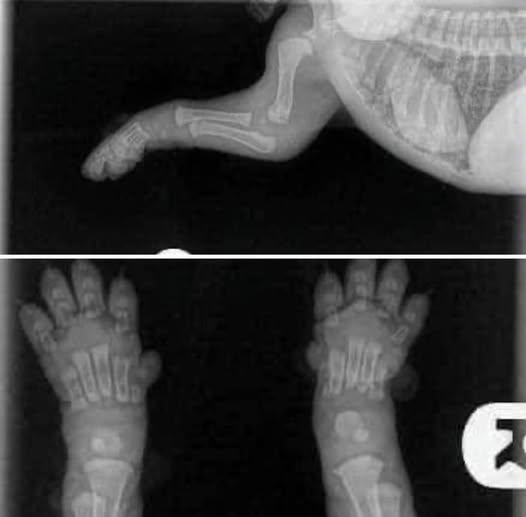

Take a look at this x-ray of a healthy golden retriever puppy. It depicts how fragile they are. We and our friends at Spice of Life Golden Retrievers would like to warn all new puppy parents to understand the following:

“This is something everyone should see!

When you get your 8/10 week old puppies, please keep this image in mind. Their bones do not even touch yet. They plod around so cutely with big floppy paws and wobbly movement because their joints are entirely made up of muscle, tendons, ligaments with skin covering. Nothing is fitting tightly together or has a true socket yet.

When you run them excessively or don’t restrict their exercise to stop them from overdoing it during this period you don’t give them a chance to grow properly. Every big jump or excited bouncing run causes impacts between the bones. In reasonable amounts this is not problematic and is the normal wear and tear that every animal will engage in.

But when you’re letting puppy jump up and down off the lounge or bed, take them for long walks/hikes, you are damaging that forming joint. When you let the puppy scramble on tile with no traction you are damaging the joint.

You only get the chance to grow them once. A well built body is something that comes from excellent breeding and a great upbringing-BOTH, not just one.

Once grown you will have the rest of their life to spend playing and engaging in higher impact exercise. So keep it calm while they’re still little baby puppies and give the gift that can only be given once” –Spice of Life Golden Retrievers